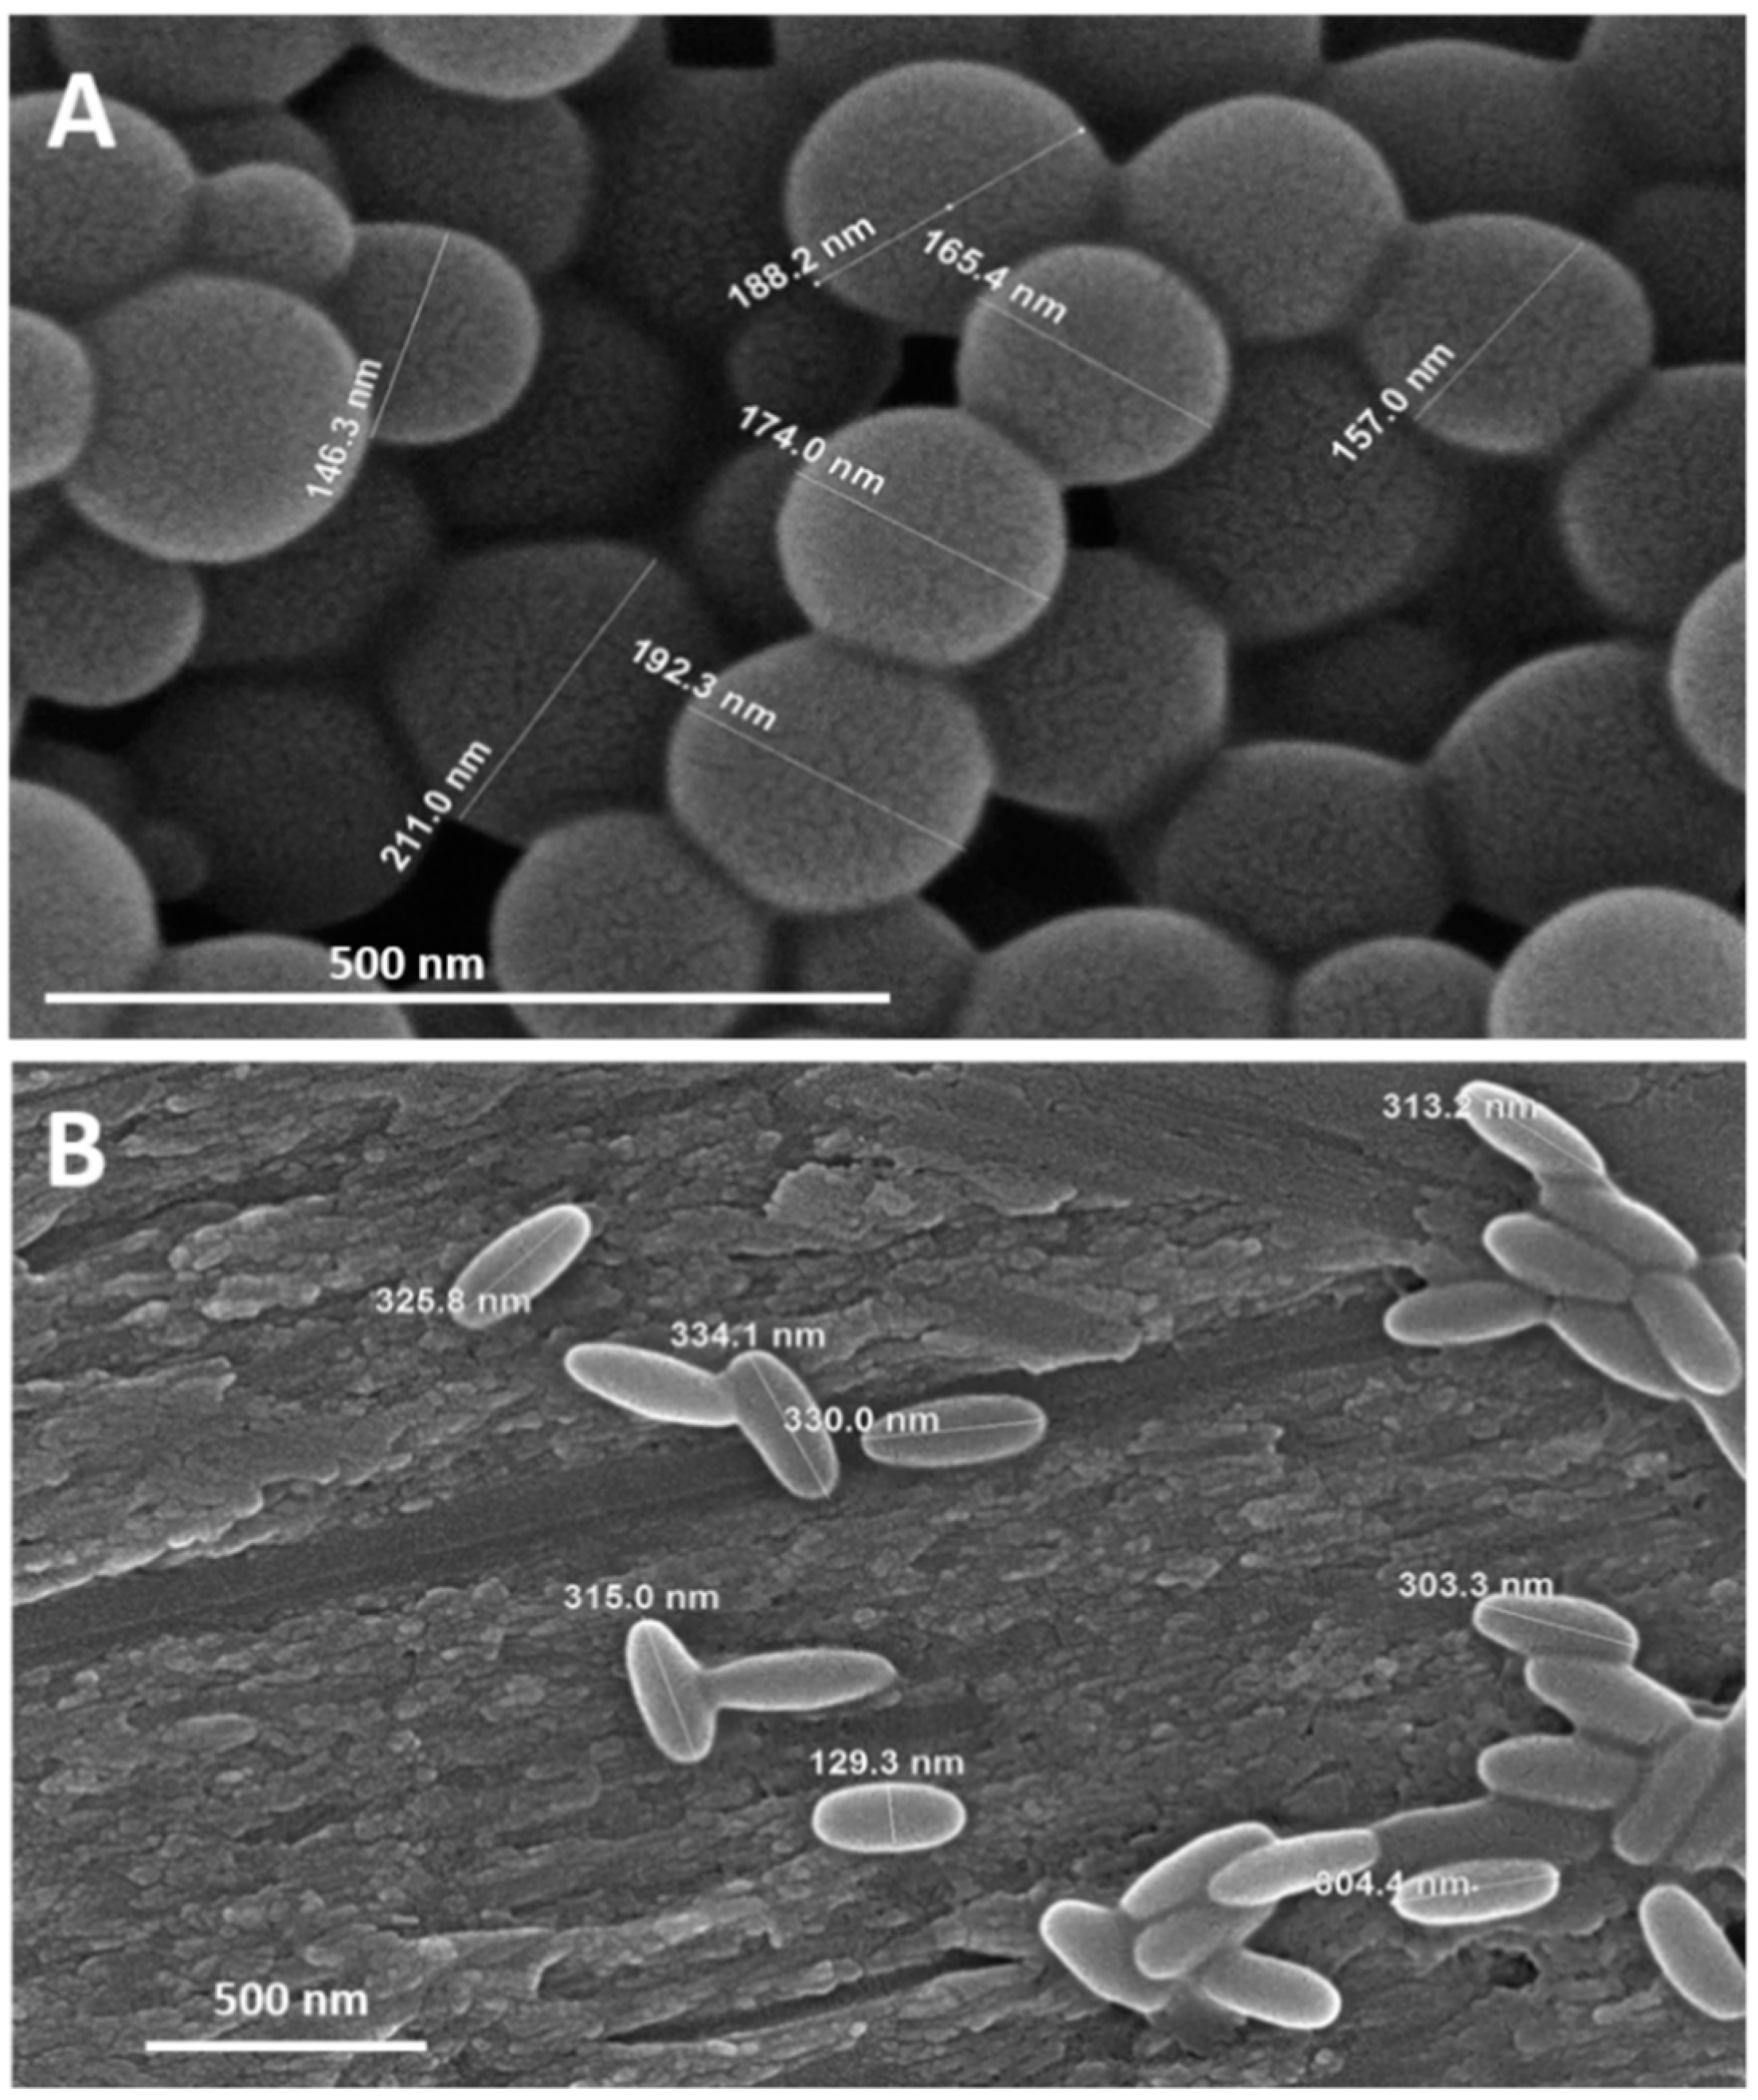

3.2. Clot Targets for rtPA Nanocarrier Vectorization

- Da Silva-Candal, A.; Brown, T.; Krishnan, V.; Lopez-Loureiro, I.; Ávila-Gómez, P.; Pusuluri, A.; Pérez-Díaz, A.; Correa-Paz, C.; Hervella, P.; Castillo, J.; et al. Shape effect in active targeting of nanoparticles to inflamed cerebral endothelium under static and flow conditions. J. Control. Release 2019, 309, 94–105. [Google Scholar] [CrossRef]